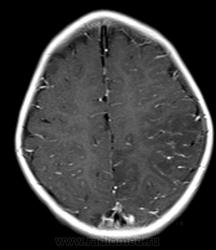

А что еще нужно? Диффузия есть, какой-то не очень понятный flair, зона изменений на них идентична Т2ВИ. По РКТ перед этим заподозрили арахноидальную кисту, диф с менингиомой задней трети серпа.

Артериальный инфаркт в бассейн не умещается, тут и сма и пма. Синусы на взгляд проходимы. Так что мне кажется больше за энцефалит. Оболочки правда не утолщены (если менингоэнцефалит).

На DWI зона умеренно сниженой диффузии, по размерам и структуре идентичная зоне изменений на Т2ВИ. Ни больше ни меньше.

Анамнез не дочитал сначала. За опухоль на мой взгляд данных нет вообще. Изменения идут по коре на большом протяжении с небольшой относительно зоной отёка белого вещества. Так что менингоэнцефалит наиболее вероятен. Анамнез ликвора на мой взгляд обязателен, хотя я и не невролог.

Я бы в дифряд еще гипоперфузию добавил (визуально похоже на PRES, но локализация иная)... Что там с магистральными сосудами? Ангио делали?

Масс-эффект есть - присмотритесь к бороздам на Т1. Есть поражение и коры, и белого вещества - такое бывает при нарушении кровотока по мелким сосудам. Снижение диффузии (я так понимаю, ADC снижен?) как раз говорит о цитотоксическом отеке и характерно для инфаркта. Единственное, что смущает - это вовлечение бассейна ПМА. Но, во первых, эти бассейны у людей вариабельны, и вполне может оказаться, что медиальные отделы полушария кровоснабжаются у этого пациента из СМА. А во-вторых, если есть патология сосудов, то почему бы и не поражение 2 бассейнов сразу? Так что, я не вижу тут ничего, что бы не укладывалось в инсульт. А посему пользуемся бритвой Оккама.